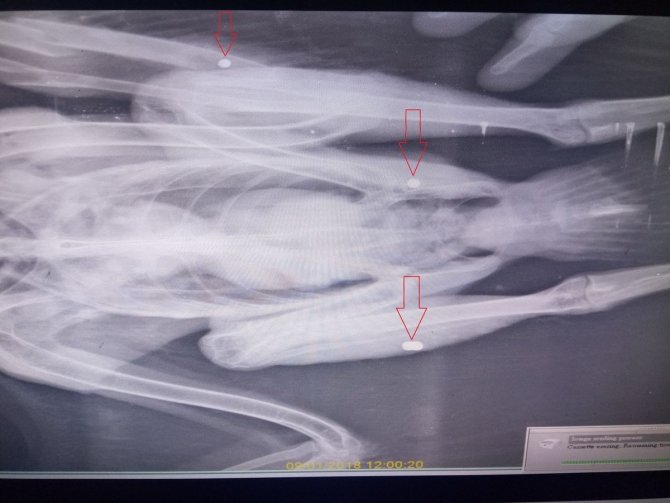

Vatandaşları, gökyüzünün efendilerine karşı daha dikkatli ve duyarlı olmaya davet eden EKODOSD Başkanı Bahattin Sürücü; "Ekosistemin önemli parçaları olan yırtıcı kuşların zaman zaman duyarsız kişiler tarafından ateşli silahlarla vuruldukları görülmektedir. Bu tür yırtıcı kuşlar genellikle kümes hayvanları ya da güvercinlere saldırıyor gerekçesiyle ya da canlı denek olarak vurulmakta, tedavi sonrası bazıları doğaya geri dönmekte, bazılarıysa uçamadıklarından bakıma muhtaç hale gelmektedir. Veterinerlik Fakültesinde daha önce vurulan kuşların röntgen filmlerine bakıldığında, ateşli silahlara maruz kalan yırtıcı kuşların vücutlarında birçok saçmaların görüldüğü, bunlardan bazılarının kanatlarına isabet etmesi sonucu uçma yeteneğini kaybettikleri görülmektedir. Şahin gibi yırtıcı kuşların, fare gibi tarım zararlılarını tüketmesi nedeniyle, çiftçilere çok yararı olmaktadır. Doğal denge içinde önemli işlevi bulunan yırtıcı kuşların korunması için, vuranlara mutlaka gerekli yaptırımlar uygulanmalı ve bilgilendirmenin sürekliliği sağlanmalıdır" dedi.